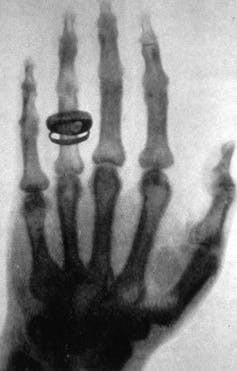

Los descubrimientos de otros tipos de ondas electromagnéticas se fueron sucediendo durante el siglo XIX y principios del siglo XX: ondas de radio y microondas (Heinrich Rudolf Hertz, 1887), rayos X (Wilhelm Conrad Röntgen, 1895) y rayos gamma (Paul Ulrich Villard, 1900).

Los rayos X pueden producirse mediante desaceleración de electrones al chocar con un blanco o a través de transiciones electrónicas entre orbitales internos de un átomo o molécula. Por otro lado, la luz visible se produce normalmente mediante transiciones electrónicas entre orbitales externos de un átomo o molécula.